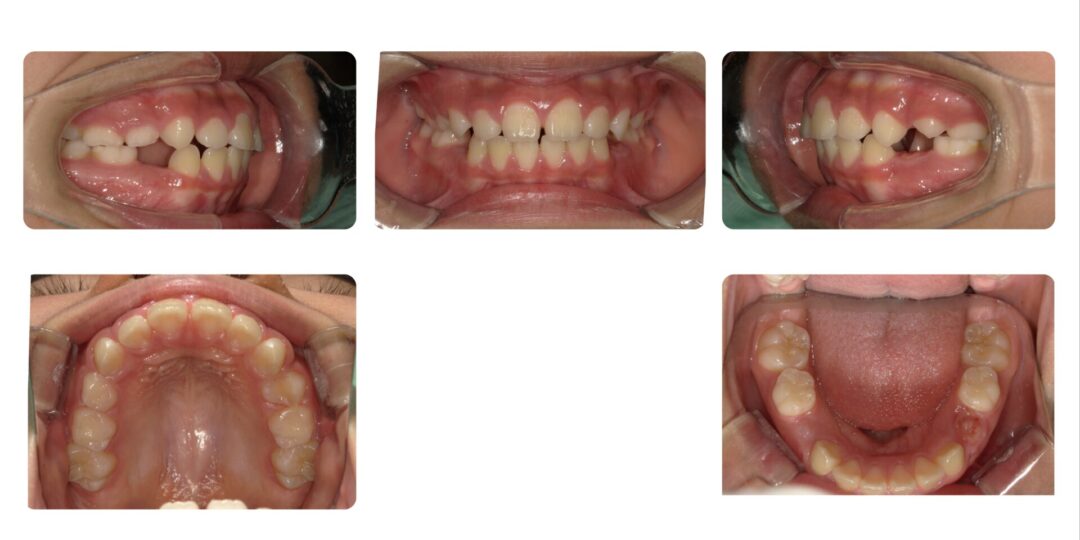

矯正治療前

ご相談内容

上の歯2本が前に出ているのが気になる。

初診時7歳

治療内容

第一期治療 拡大ねじ付きバイオネーター

治療期間

1年9か月

治療費用

自由診療 基本料金¥330,000 処置料¥3,300